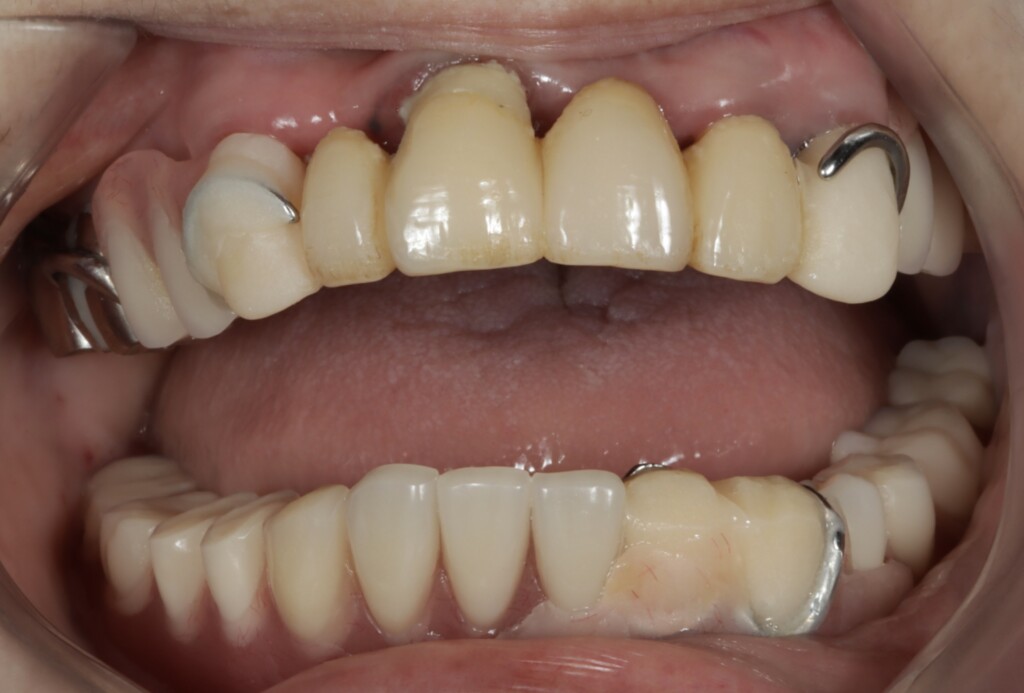

治療前の状態

写真1:口腔内の正面観

*下顎は部分入れ歯を修理した総入れ歯が装着されている

写真2:乱れた噛み合わせの平面

①下顎義歯が歯ぐきの形や機能に合っていないため動いてしまう

写真1・2の下顎の義歯は、もともと部分入れ歯として使用されていたものを、抜歯に伴い修理し、総入れ歯として使用されていました。総入れ歯と部分入れ歯は同じ「入れ歯」ですが、設計のコンセプトは大きく異なります。

総入れ歯は、単に歯ぐきの形に合っているだけでは安定しません。つかむ歯が周囲に存在しないため、安定して使用するためにはいくつかの重要なポイントがあります。

今回の義歯は、もともと部分入れ歯として作製されたものを修理して使用していたため、こうした「総入れ歯としての安定に必要な設計」が十分ではありませんでした。その結果、食事のたびに動いてしまう状態につながっていたと考えられます。

②上顎の残存歯に虫歯と歯ぐきの炎症が認められ、支える力が低下している

上顎は、前歯部にブリッジ、右上奥歯には銀の被せ物が装着されている状態でした。しかし、それらを支えているご自身の歯との境目から虫歯が進行しており、残っている歯のほぼすべてに問題が認められました。特に右上の前歯は、歯ぐきの下にまで虫歯が進行しており、汚れが溜まりやすい状態となっていたため、歯ぐきにも強い炎症がみられました。また、その他の歯についても、虫歯ではない健全な歯質が歯ぐきの縁付近までしか残っていない状態で、歯としての支える力が大きく低下していました。

③上下の入れ歯の噛み合わせの平面が著しく乱れていて、歯にかかる力のバランスが崩れている

①とも関連しますが、上下の入れ歯の噛み合わせの平面が乱れていると、噛んだときに一部だけが先に強く当たり、力のかかり方が偏ってしまいます。その結果、入れ歯がテコのように動き、反対側が浮き上がるなど、不安定な状態になります。これは、テーブルの脚の高さが揃っていないとガタつくのと同じで、噛み合わせのバランスが崩れることで、入れ歯全体の安定性が大きく低下してしまうのです。